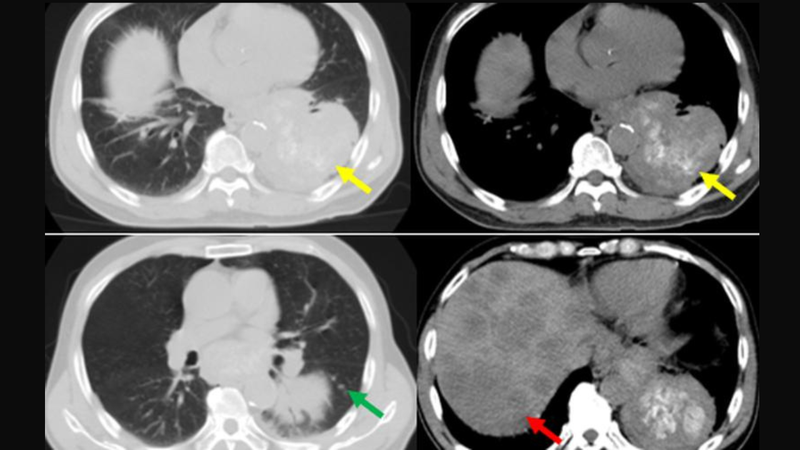

Ngoài ra, việc thực hiện chụp cắt lớp vi tính phổi có thể hữu ích hơn trong việc chẩn đoán khối u phổi so với việc sử dụng chụp X-quang phổi thông thường. Bằng cách này, bác sĩ có thể xác định vị trí, kích thước và hình dạng của khối u phổi, cũng như kiểm tra sự hiện diện của các hạch bạch huyết hoặc dấu hiệu lây lan của tế bào ung thư từ phổi.

Quá trình chụp bao gồm việc chụp toàn bộ phần lồng ngực từ cổ đến cơ hoành, sau đó chụp các lớp cắt liên tiếp từ đỉnh phổi đến góc sườn hoành, với độ dày lớp cắt thường từ 1 - 2mm.

Chụp cắt lớp vi tính phổi là một trong những kỹ thuật chẩn đoán hàng đầu cho việc phát hiện các bệnh lý liên quan đến phổi, đặc biệt là khối u phổi. Kỹ thuật này mang lại giá trị chẩn đoán cao bằng cách tạo ra hình ảnh chi tiết và rõ ràng về cấu trúc bên trong phổi, giúp bác sĩ phát hiện sớm các dấu hiệu của khối u phổi, bao gồm cả các khối u lành tính và ác tính.